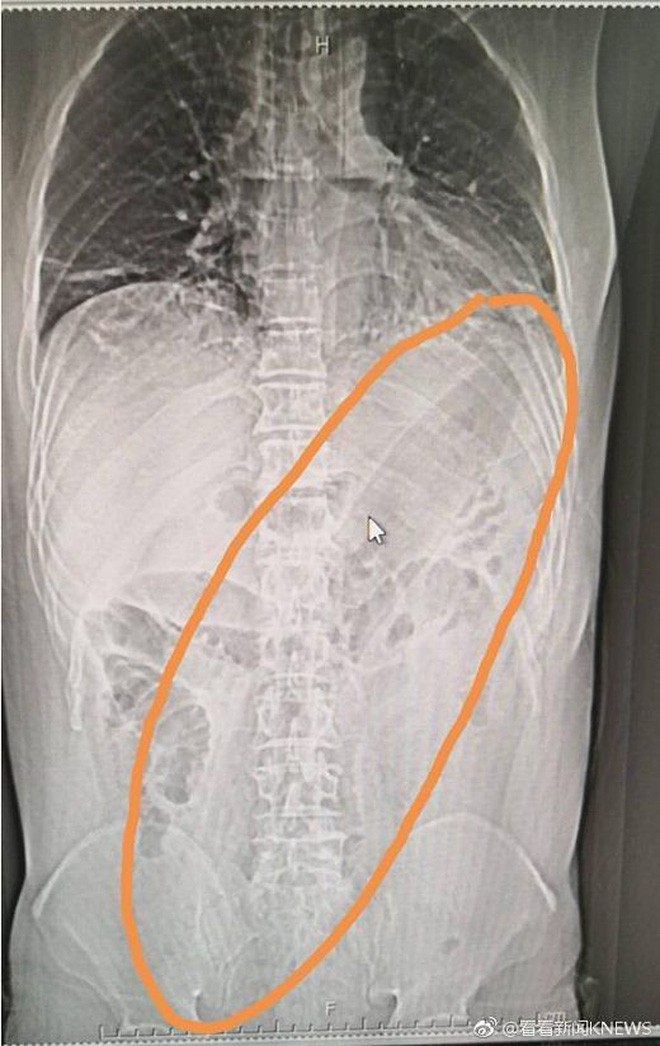

Hình ảnh chụp ích quang vị trí quả cả tím trong cơ thể người đàn ông.

Tại bệnh viện, hình ảnh X-quang cho thấy quả cà tím khổng lồ được đẩy vào mông người đàn ông đã gây ảnh hưởng đến phổi. Các bác sĩ tại bệnh viện phải tìm cách để rút dị vật ra ngoài. Tại đây, người ta đo được quả cà tím dài đến 30cm.

Quả cà tím dài 30 cm.